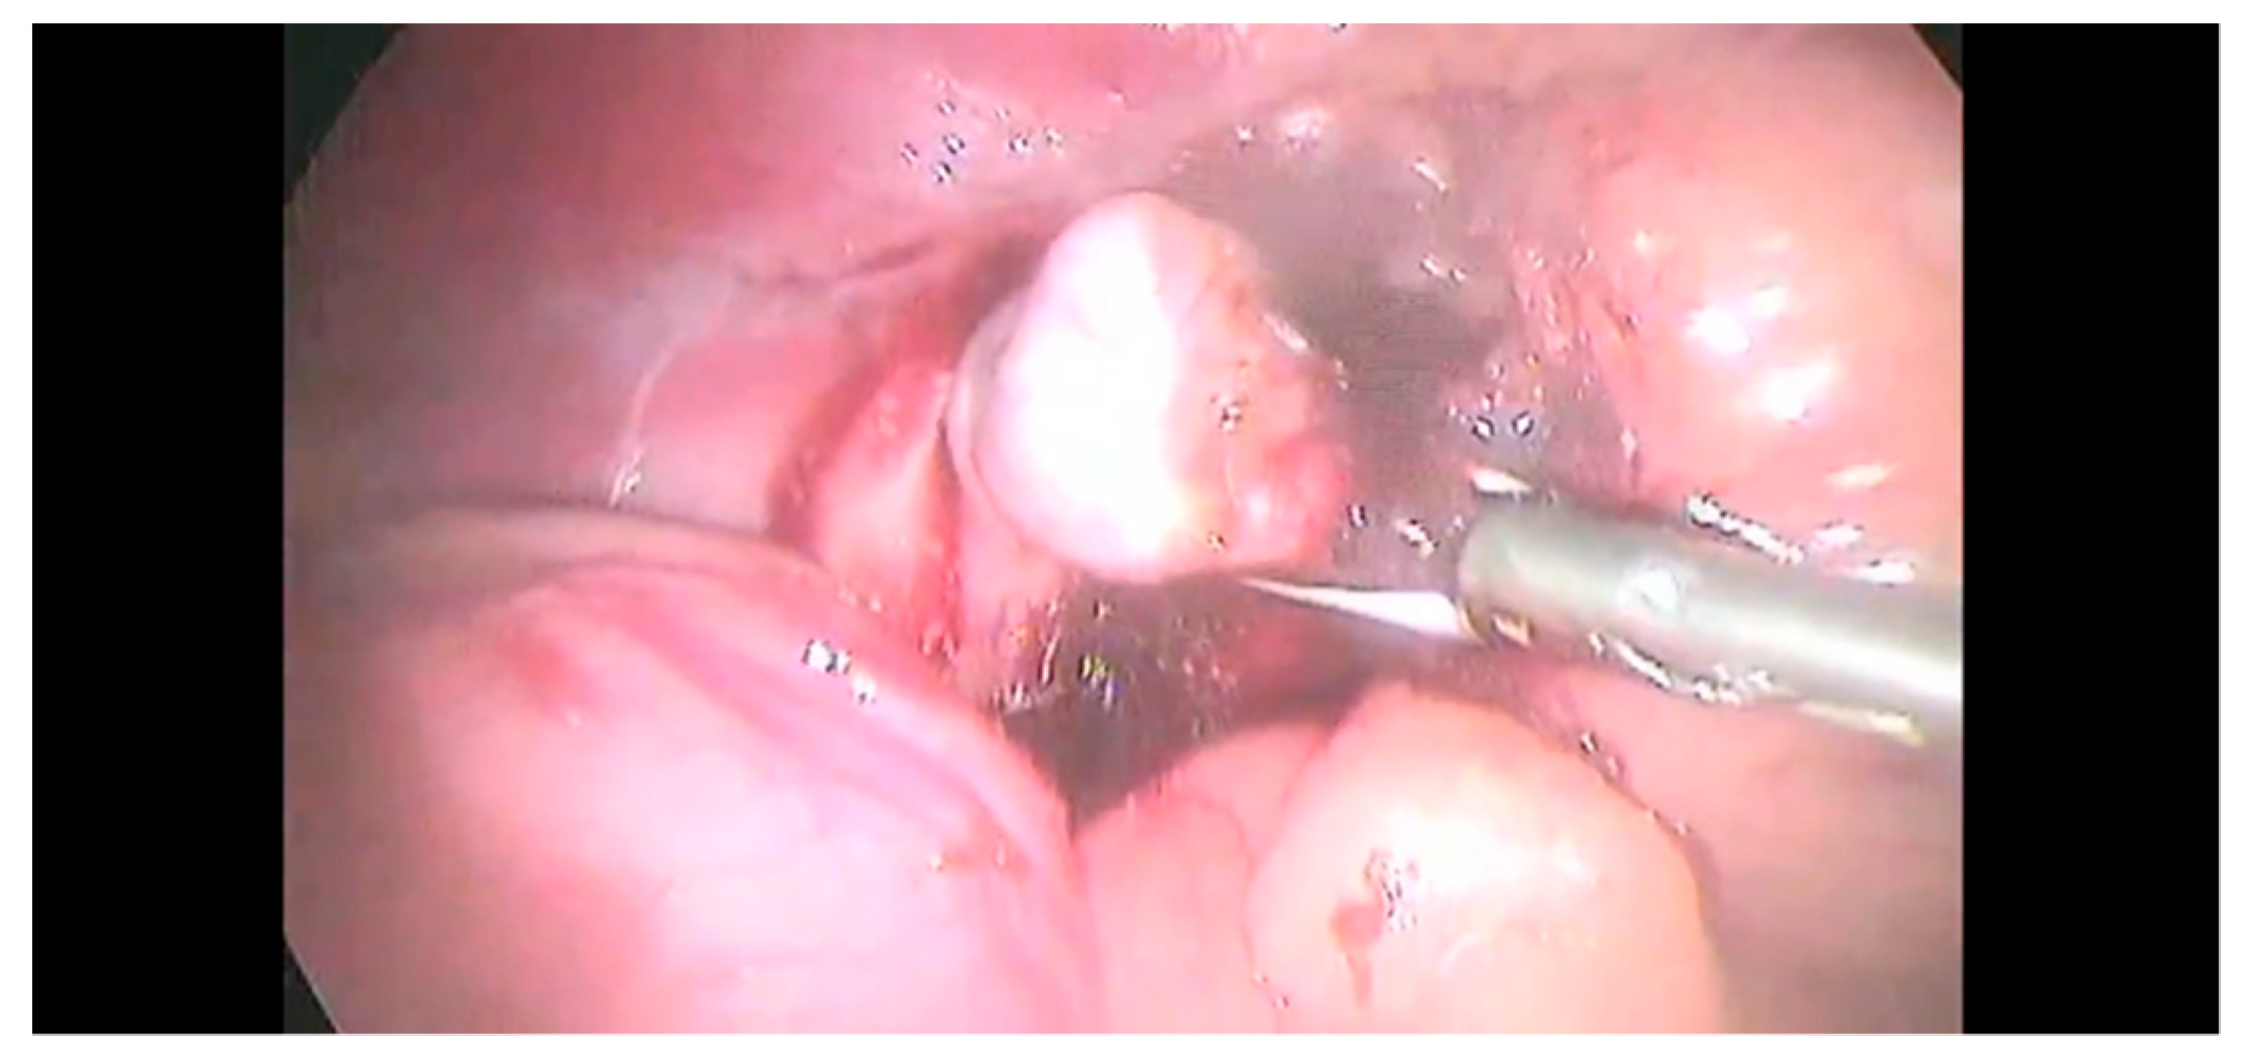

2.2. Surgical Procedure